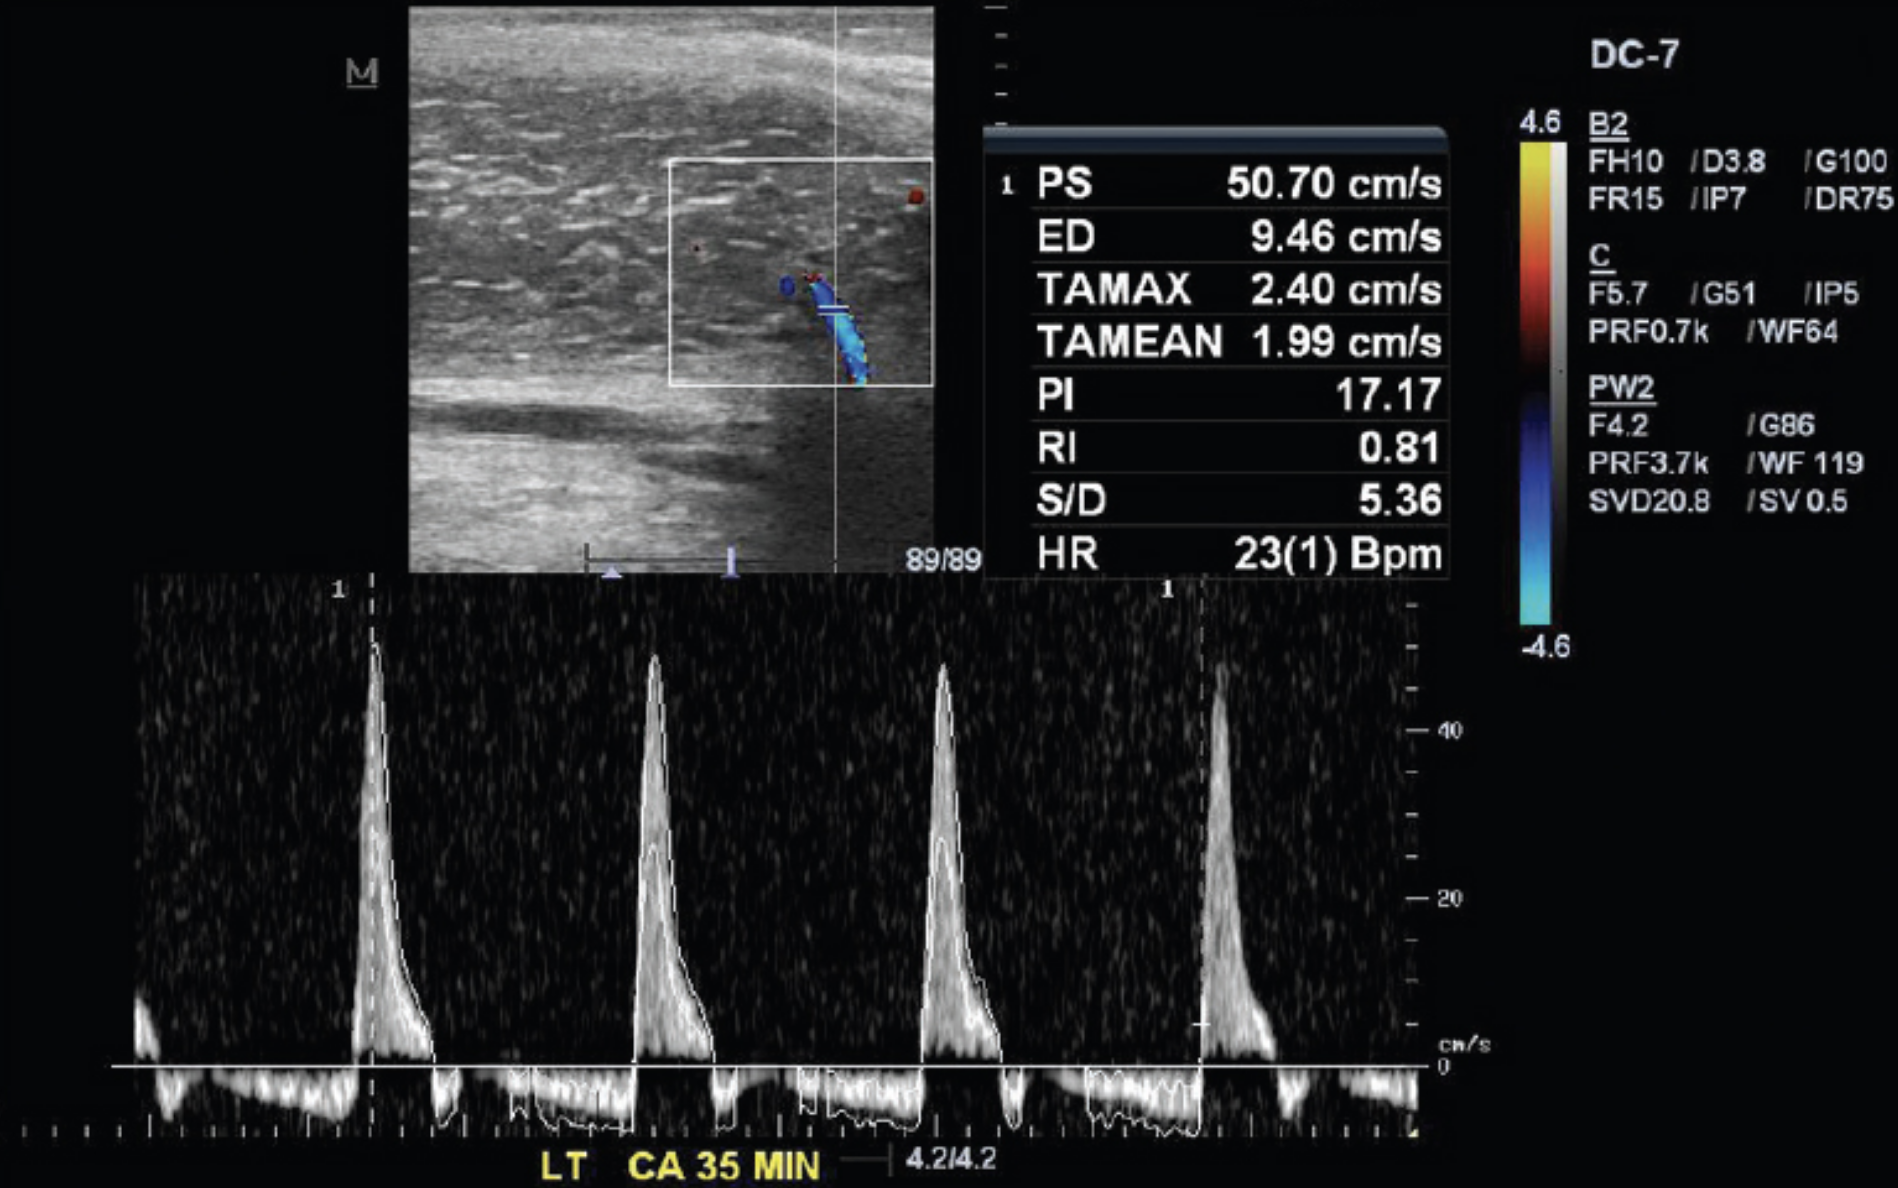

Penile Ultrasound Dysfunction Detection — Fairbanks Urology Ultrasound Machine For Erectile Dysfunction penile ultrasound and duplex doppler, enables characterization of arterial and venous blood flow within the erect penis. penile duplex doppler ultrasound (pddu) has become a key diagnostic tool in the evaluation of erectile dysfunction (ed) and. penile doppler sonography is an essential tool for differentiating between vascular and nonvascular. lipus is most effective in men with. Ultrasound Machine For Erectile Dysfunction.